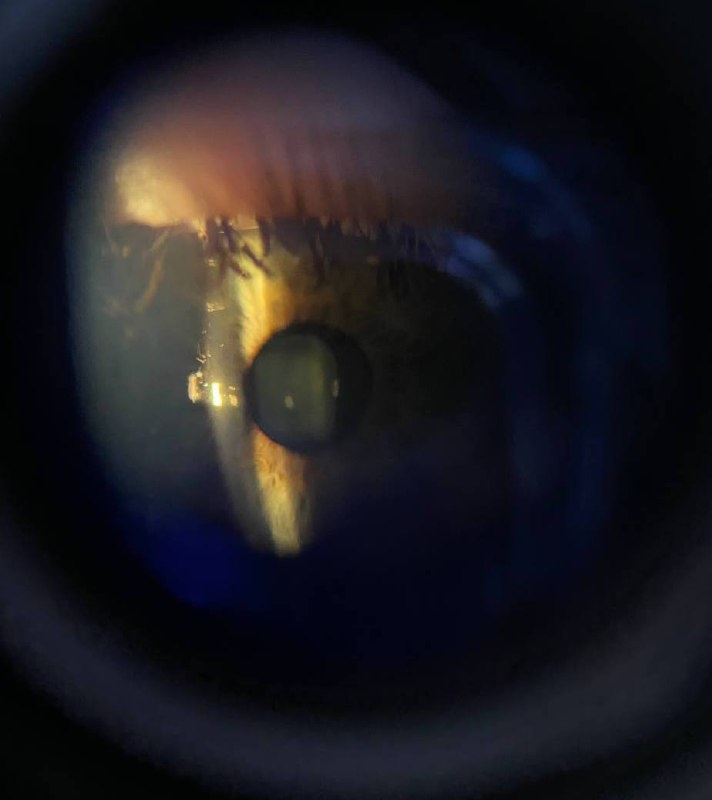

В прошлом году на паре по офтальму у меня нашли врождённую катаракту🤯 (на фото, светлое пятнышко)